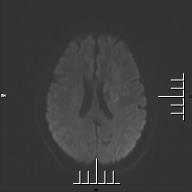

患者入院后,醫(yī)院高度重視,由醫(yī)務(wù)科組織神經(jīng)外科、麻醉科、急診科、ICU等科室會(huì)診討論,制定詳細(xì)的治療方案。9月25日,在南京鼓樓醫(yī)院專家的指導(dǎo)下,我院神經(jīng)外科成功為該患者實(shí)施了我院首例“顳淺動(dòng)脈-大腦中動(dòng)脈搭橋術(shù)”?;颊咝g(shù)后神志清楚,無腦出血、腦梗死等并發(fā)癥,四肢活動(dòng)正常,術(shù)后復(fù)查頭顱MRA顯示:顳淺動(dòng)脈-大腦中動(dòng)脈吻合血管通暢。術(shù)后9天出院。

術(shù)后第5天查MRA示:顳淺動(dòng)脈-大腦中動(dòng)脈吻合血管通暢(箭頭所示)。